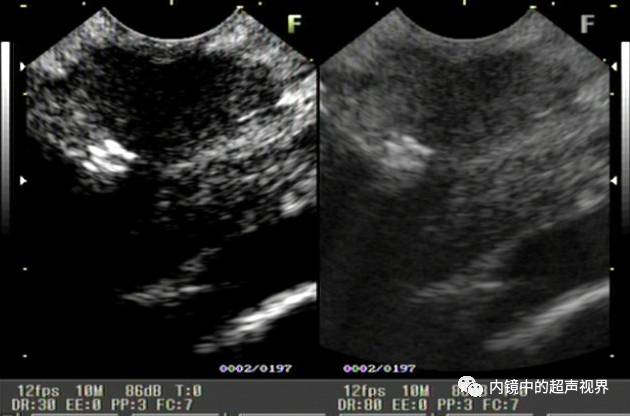

再来一纵隔肿物的图片,是DR30和80的对比,很明显。

纵隔肿物